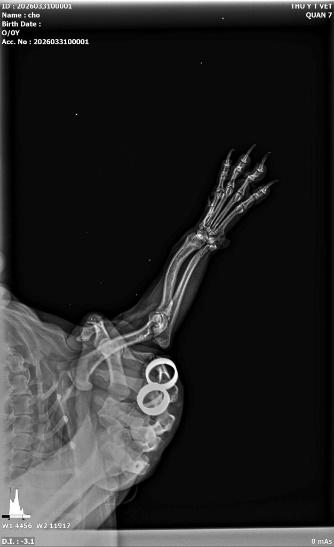

Đây là ứng dụng phổ biến nhất của X-quang. Từ những va chạm nhỏ đến các tai nạn giao thông nghiêm trọng, việc kiểm tra cấu trúc xương là bắt buộc. Dịch vụ X-quang giúp bác sĩ xác định:

• Vị trí gãy xương chính xác (xương đùi, xương chậu, xương trụ...).

• Kiểu gãy: Gãy cành tươi, gãy phức tạp, hay gãy hở.

• Độ lệch của các đầu xương để tiến hành phẫu thuật kết hợp xương (đóng đinh, bắt vít) hiệu quả nhất.

.jpeg)

Hình ảnh: chân vòng kiềng, ở các bé chân ngắn

Hình ảnh: gãy xương trụ và xương quay trước